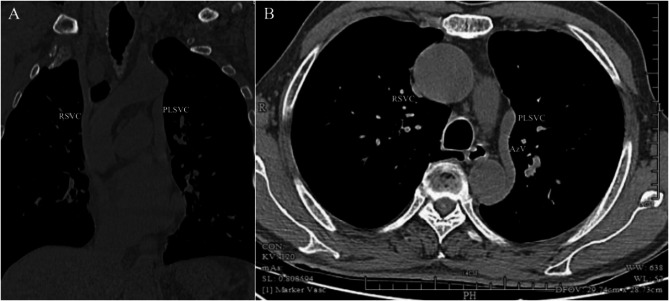

Venous Port implantation in persistent left superior vena cava with azygos vein variation: a case report and literature review.